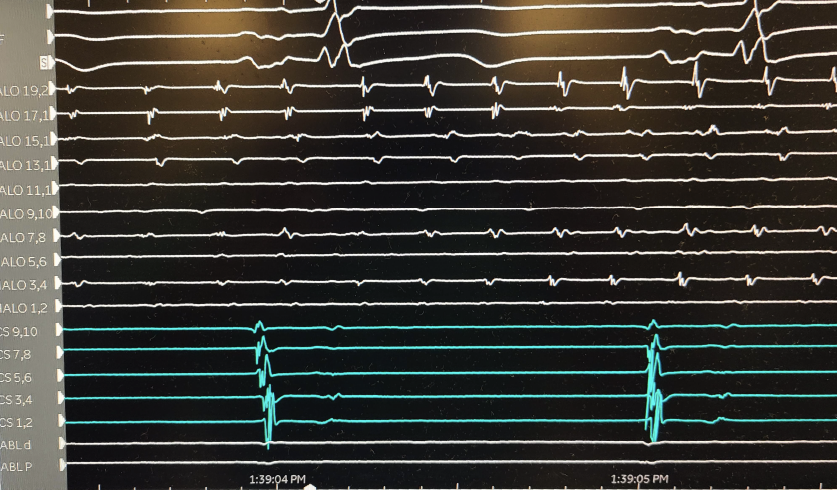

Difficult mitral isthmus line after mitral flutter induced post atrial fibrillation ablation. Intermittent block with multiple endocardial burns. Bidirectional block after VOM injection with dramatic increase in endocardial scar on right @VirtuaHealth @VirtuaHRS @AatishGarg_EP

@AatishGarg_EP @VirtuaHealth @VirtuaHRS @jaykoneru @KennethEllenbo1 @MiguelVldrbno @EPbordeaux @HeathHsalt Great work on first case. 3 minutes of endocardial burns to get bidirectional mitral isthmus block is no joke

Delighted to start the Vein of Marshall alcohol ablation program at @VirtuaHealth with @VirtuaHRS Grateful to @jaykoneru and @KennethEllenbo1 for their guidance along with @MiguelVldrbno and @EPbordeaux for their groundbreaking research articles.